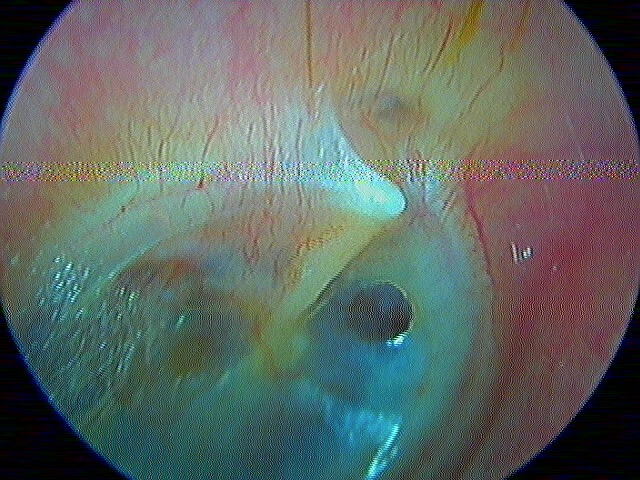

3/2 barotraumatique

– stade I : hyperhémie du manche du marteau et de la pars flaccida ;

– stade II : tympan rétracté, congestif, immobile

– stade III : aspect d'otite séromuqueuse

– stade IV : aspect otite séro-hémorragique, otohématome

– stade V : perforation

Ici des stades V perforés